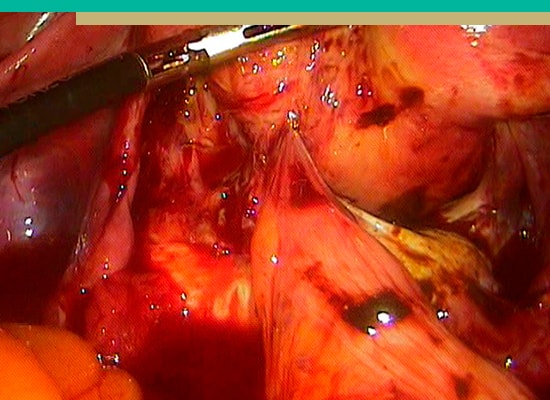

Endometriosis

Es una enfermedad ginecológica crónica en las que existe tejido endometrial fuera del útero. Este tejido se encuentra principalmente en la pelvis. Afecta al 10% de las mujeres en edad reproductiva.